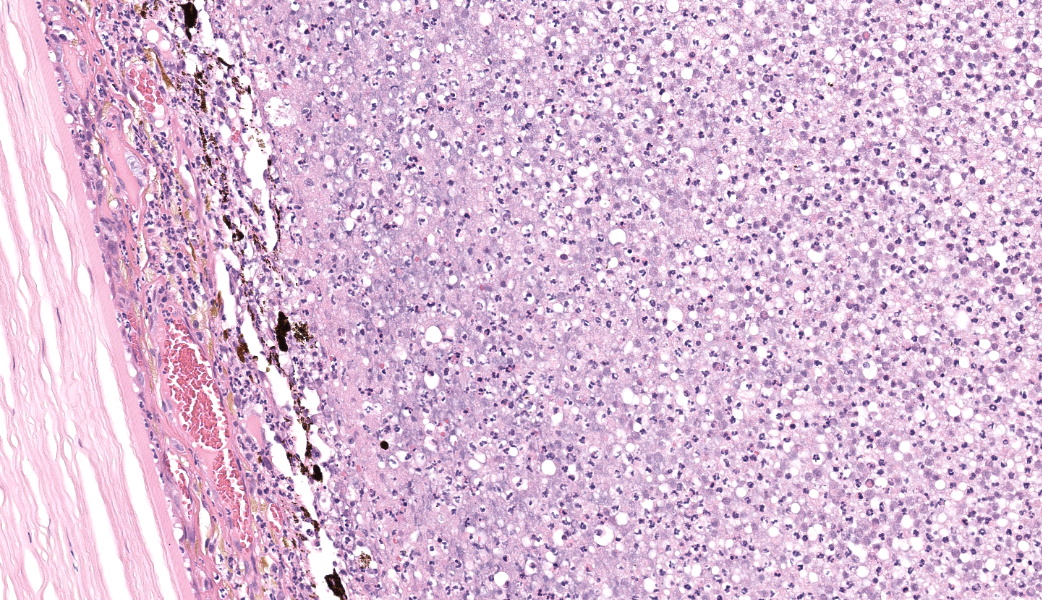

Filling all ocular chambers and coating the surfaces of intraocular structures are vast accumulations of exudate consisting of myriad degenerate and intact neutrophils, many macrophages, abundant amounts of fibrinous to proteinic material, abundant necrotic cellular debris, occasional pools of extravasated erythrocytes, and multifocal colonies of mixed bacteria (rods and coccobacilli). Centrally incorporated into the inflammatory exudates is a ruptured lens which lacks a capsule in many areas and has highly undulating free capsule margins regionally. The lenticular stroma is variably vacuolated with the following features: streaks of pallor, Morgagnian globules, many infiltrating leukocytes (mostly neutrophils), and occasional pockets of similar bacteria. The retina is diffusely detached and largely inapparent apart from remnant segments of atrophied and degenerate retina enmeshed within the exudate. Suppurative to pyogranulomatous inflammatory infiltrates multifocally extend into the iris, ciliary body, choroid, optic nerve which is significantly gliotic with rarefied neuropil, and optic nerve meninges. The iris is displaced anteriorly and multifocally abuts the posterior aspect of the cornea. The anterior chamber is severely narrow, and the drainage angle is collapsed and inapparent. The corneal stroma is moderately to markedly oedematous and contains small to moderate numbers of scattered neutrophils. The anterior corneal epithelium appears attenuated in areas. The sclera is variably thinned with multifocal often perivascular infiltrates of lymphocytes and plasma cells with variable numbers of admixed neutrophils and occasional macrophages. There are increased numbers of perilimbal pigmented cells. A thin to moderately thick layer of oedematous and inflamed granulation tissue regionally lines the mid and posterior scleral margins outside the globe and extends into a bundle of periocular skeletal muscle. In addition to infiltrates of the aforementioned inflammatory cells, the granulation tissue also contains many golden-brown pigmented macrophages (siderophages) which are concentrated at the level of the ciliary body. There is abundant haemorrhage in the retrobulbar loose connective tissue.Contributor's Morphologic Diagnoses:

Endophthalmitis, diffuse, suppurative to pyogranulomatous, severe, with lens rupture, retinal detachment and degeneration/atrophy with intraocular exudation and intralesional mixed bacteria, drainage angle collapse, keratitis, corneal oedema, scleritis and regional periscleral fibrosisContributor's Comment:

Globe: Endophthalmitis, fibrinosuppurative, subacute, diffuse, severe, with lens rupture, synechiae, fibrovascular membranes, retinal detachment and atrophy, and bacterial colonies.JPC Comment:

Talk about a descriptive case that made, for obvious reasons, an excellent sales pitch on why pathology is the best profession! This case provides an excellent opportunity for participants to push themselves on their ocular descriptive abilities. Many thanks to this contributor for a fantastic case! Much like the previous eye case in this conference, there was substantial discussion on ocular pathology. The most informative nuggets from that conversation included utilizing the lens capsule, which is an easily identifiable structure in the eye, to assist with orientation in a busy ocular slide such as this one. The pigmented irideal stroma, as well as the “golden” fibers of the iris, can also be used to help identify structures that might otherwise be difficult to ascertain due to the degree of damage and/or inflammation.This case had beautiful examples of iris bombe (iris pushed forward into the anterior chamber and adhered to the back of the cornea), numerous types of fibrovascular membranes (retrocorneal, preiridial, cyclitic, etc.), and a fantastic phakoclastic panuveitis from lens rupture. The six types of uveitis and their definitions were discussed and included: 1) anterior uveitis (inflammation of the iris and ciliary body), 2) posterior uveitis (inflammation of the ciliary body and choroid), 3) panuveitis (iris, ciliary body, and choroid affected), 4) chorioretinitis (inflammation of the choroid and retina), 5) endophthalmitis (inflammation of uvea, retina, and ocular cavities), and 6) panophthalmitis (all ocular structures are affected, including sclera). Being able to recognize and accurately use these terms as pathologists can provide crucial information to ophthalmologists when it comes to treating these patients.